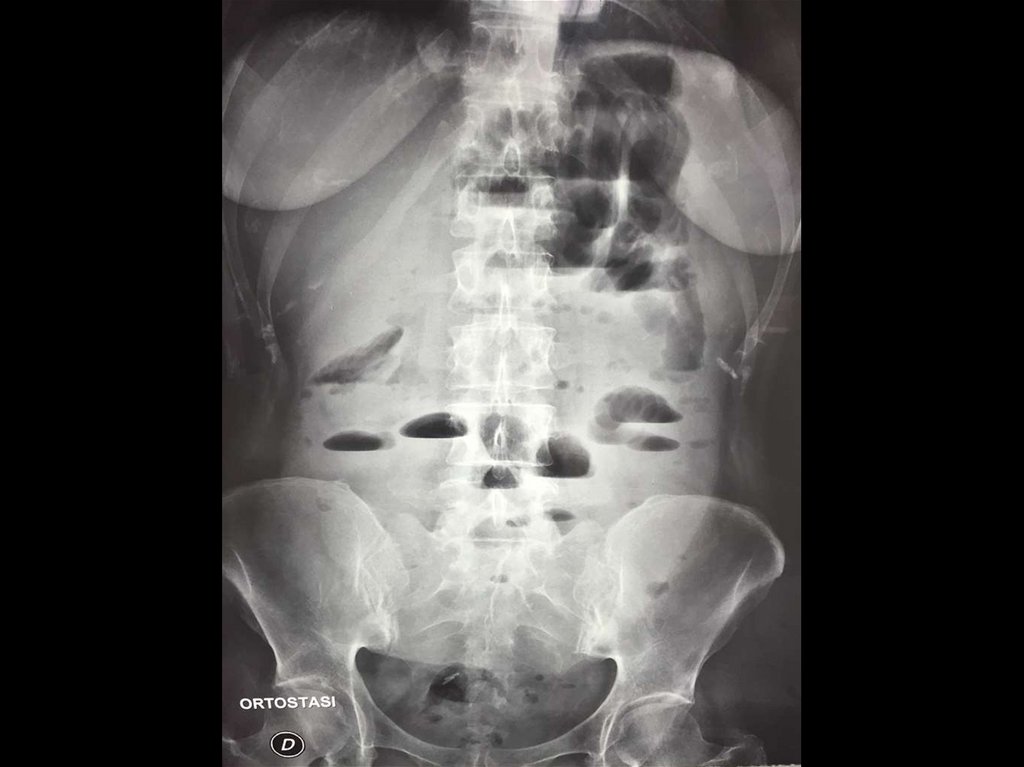

96. Острый живот - кишечная непроходимость.

ОСТРЫЙ ЖИВОТ - КИШЕЧНАЯ

НЕПРОХОДИМОСТЬ.

Этапы рентгенологического исследования.

- Обзорная рентгенограмма брюшной полости

при вертикальном положении больного;

- Выявление уровней жидкости в проекции петель

кишечника – «чаши Клойберга».

- При механической кишечной непроходимости

для выявления уровня поражения исследование

с применением бариевой взвеси.

97. КИШЕЧНАЯ НЕПРОХОДИМОСТЬ

Динамическая кишечная

Механическая кишечная